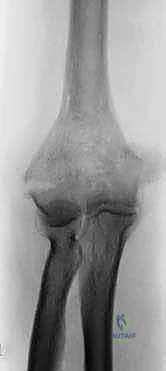

يؤمن الدكتور محمد هطيف بأن "التشخيص الدقيق هو نصف العلاج". تبدأ رحلة المريض في عيادته بتقييم سريري شامل يتضمن فحص النبض والأعصاب للتأكد من سلامة التروية الدموية والإحساس.

تتضمن الفحوصات التصويرية:

1. الأشعة السينية (X-rays): من زوايا متعددة لتحديد موقع الكسر المبدئي.

2. الأشعة المقطعية ثلاثية الأبعاد (3D CT Scan): وهي خطوة لا غنى عنها في حالات الكسور المفتتة. تساعد هذه الأشعة الدكتور هطيف في بناء خريطة جراحية دقيقة، لمعرفة حجم الشظايا العظمية، وتحديد ما إذا كان العظم قادراً على تحمل المسامير أم أن استبدال المفصل هو الخيار الأوحد.